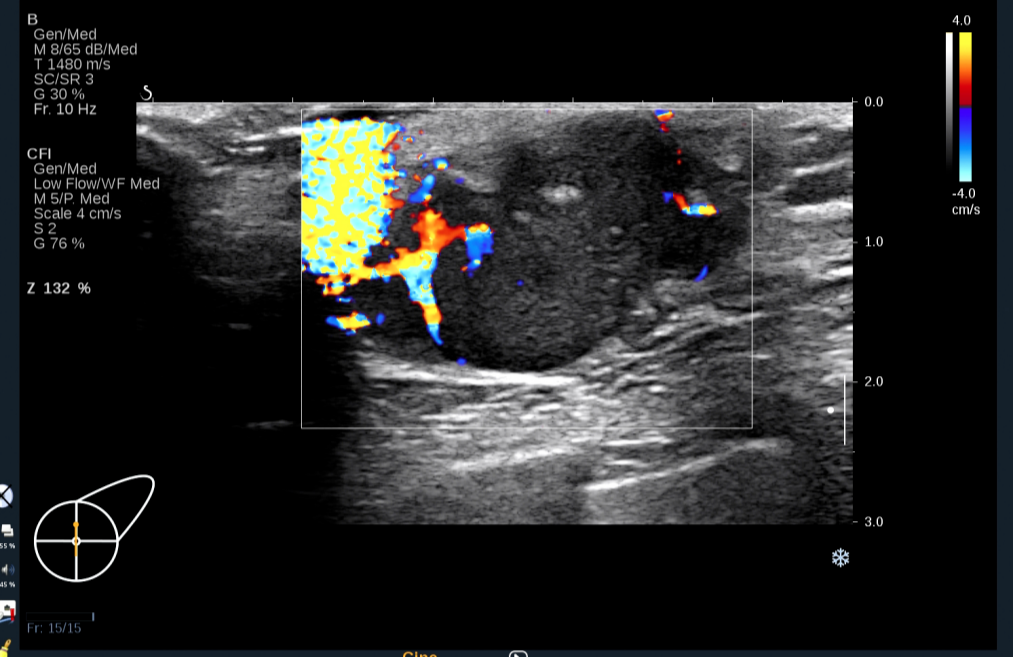

彩色多普勒及能量图:低回声团周边可见条形血流信号,并可测得动脉频谱,其内可见短棒状血流信号。

图3 彩色多普勒血流图示左乳肿块周边的粗大滋养血管

图片来源:作者提供